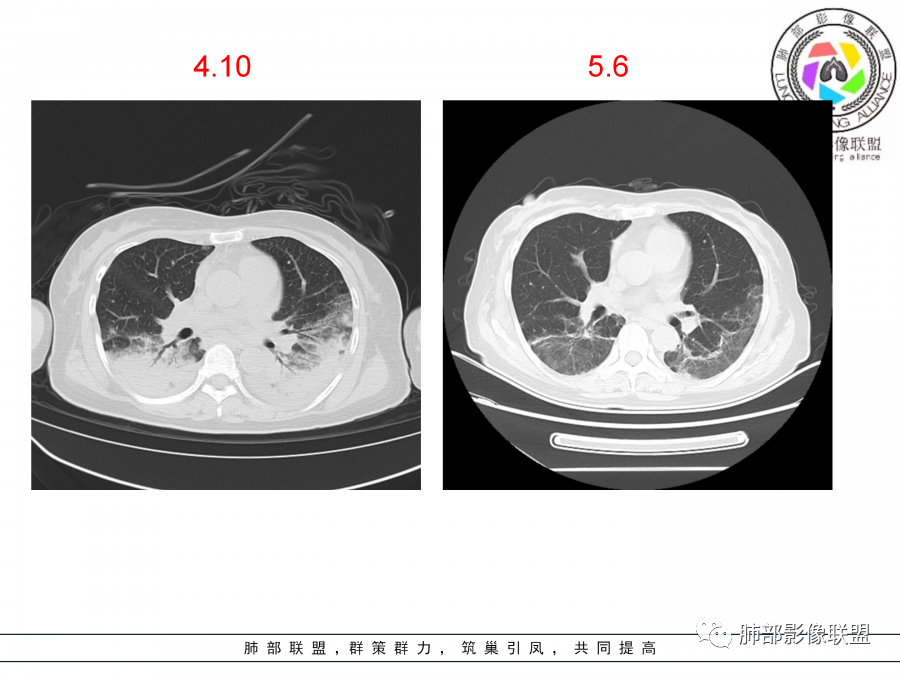

老年女性,咳嗽咳痰伴发热7天,白细胞不高,血沉快,降钙素原不高。其他化验未见明显异常,狼疮全套抗Ro/SSA阳性,双肺野靠近胸膜下磨玻璃实变影,支气管通畅,有充气征,沿胸膜下分布,有细网格征,7天后进展明显,实变影加重,胸膜肥厚,胸水不明显,心包少量积液?抗感染治疗无效,考虑非感染性疾病可能性大,结缔组织相关性肺病?狼疮性肺炎?机化性肺炎?鉴别病毒性肺炎。

老年女性,咳嗽咳痰发热7天。无气促。白细胞计数不高,PCT稍高,PPD(+),抗Ro/SSA阳性。CT:双肺野靠近胸膜下磨玻璃实变影,支气管通畅,有充气征,沿胸膜下分布,有细网格征。予抗生素治疗,8天后复查胸部CT见病灶范围扩大,实变影加重,胸膜肥厚,胸水不明显。抗感染治疗无效,考虑有:1.非感染性疾病:结缔组织相关性肺病,支持点:肺部CT表现为间质性炎症病变,抗RO/SSA(52)阳性;2.病毒性肺炎:患者无气促症状,可能性小;3.肺结核。

第一次双肺中下叶胸膜下多发斑片状磨玻璃及实变影,病变平行于胸膜,支气管通畅,8天后,双肺实变影明显进展范围扩大,部分支气管近端堵塞,进展较快,胸腔积液,抗感染治疗无效,考虑:非感染性疾病:结缔组织相关性肺病。鉴别机化性肺炎。

外围胸膜下,实变+GGO+网格,支气管通畅

提示间质为主病变